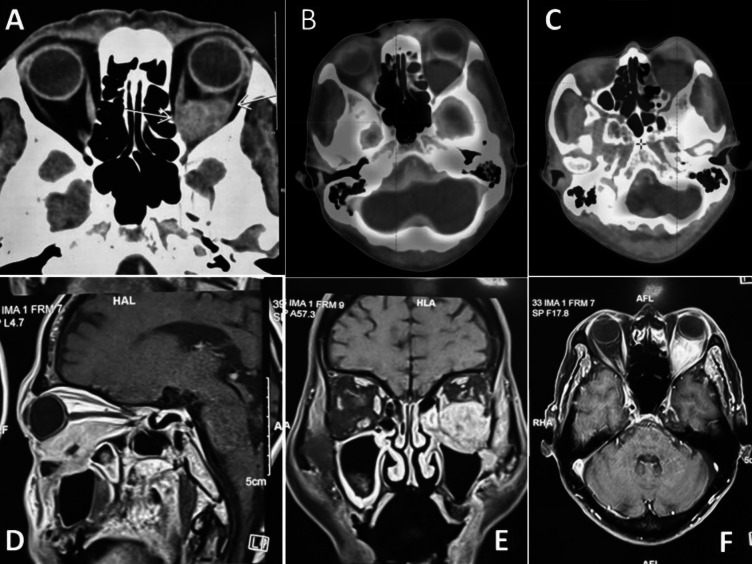

眼眶原发性鳞状细胞癌(SCC)非常罕见,仅占眼部肿瘤的一小部分,大多数病例继发于起源于附近结构的肿瘤或由于远处转移。我们报告一例60岁男性原发性眼眶鳞状细胞癌,讨论其诊断、影像学表现和多学科治疗。在认为不能手术后,患者接受了明确的放疗和同时进行的化疗。没有任何严重的治疗相关不良事件,患者在治疗后7个月获得完全的代谢反应,视力保持正常。从文献综述中可以看出,这类患者的治疗方法差异很大,放射治疗是一种成功的治疗方式,既能控制疾病,又能在可接受的毒性下保持视力。该病例强调了原发性眼眶SCCs治疗的复杂性,并强调了放疗在取得良好结果方面的有效性。

Primary squamous cell carcinoma (SCC) of the orbit is exceptionally rare, comprising only a small fraction of ocular tumours, with most cases being secondary to tumours originating from nearby structures or due to distant metastasis. We present a case of primary orbital SCC in a 60-year-old male, discussing its diagnostic workup, imaging findings, and multidisciplinary management. The patient underwent definitive radiotherapy with concurrent chemotherapy after being deemed inoperable. Without any severe treatment-related adverse event, the patient achieved a complete metabolic response at 7 months post-treatment with maintained vision. As evident from a review of the literature, treatment approaches vary widely in this group of patients, with radiotherapy emerging as a successful modality in achieving disease control while preserving vision with acceptable toxicity. This case underscores the complexity of managing primary orbital SCCs and highlights the efficacy of radiotherapy in achieving favourable outcomes.